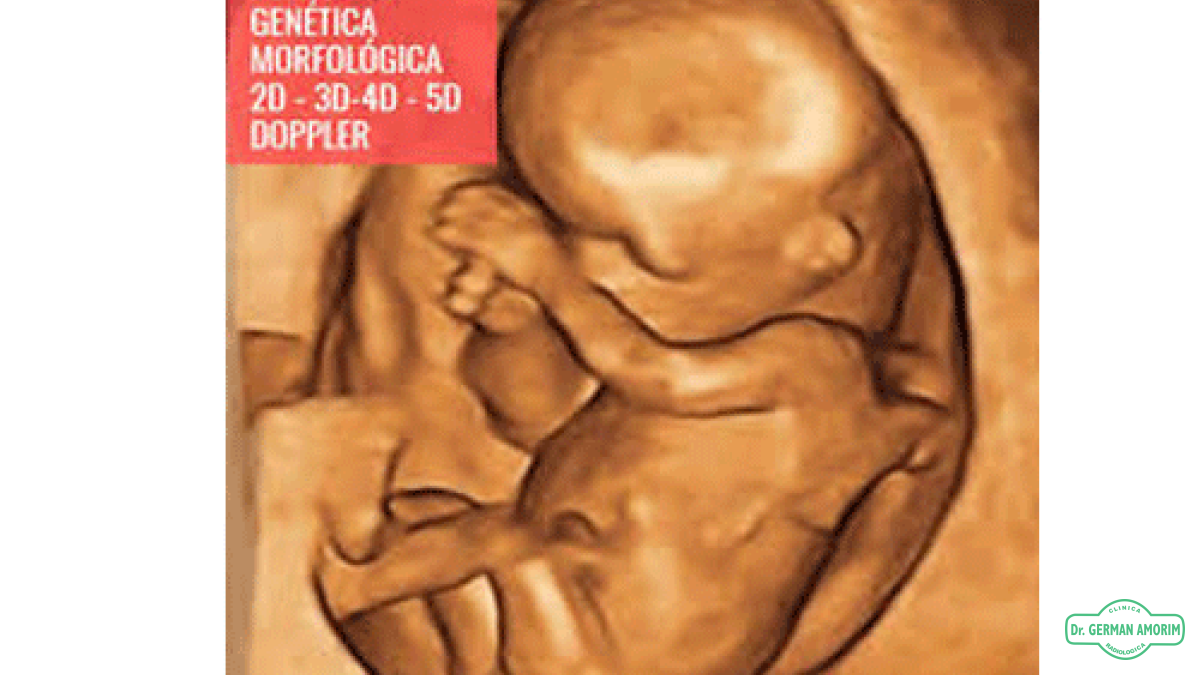

5D HDlive es una novedosa manera de visualizar a tu hij@ mediante un ecógrafo de última generación.

Es un método de reproducción extraordinario que genera imágenes asombrosamente realistas del feto humano a partir de datos ecográficos.

Mediante el uso de un modelo de iluminación avanzado, HDlive admite sombras, una fuente de luz virtual y técnicas avanzadas de representación de la piel.

Este nuevo método explota la excelente calidad de imagen proporcionada por la última generación de tecnología de formación de haces, algoritmos de reducción de manchas y tecnologías de imágenes de resolución compuesta de los sistemas Voluson S10 Expert.

HDlive se diferencia en que podemos colocar libremente una fuente de luz virtual en cualquier ángulo con respecto al volumen de ultrasonido para mejorar los detalles.

La ubicación de la fuente de luz virtual detrás de la escena mostrará el efecto de la translucidez.